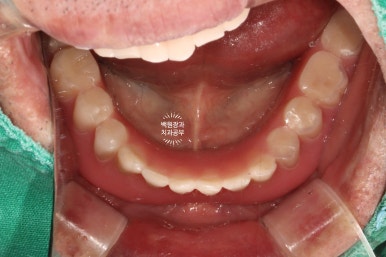

좌측이 위턱, 오른쪽이 아래턱입니다.

확인하실 수 있듯, 아래턱의 경우 단 6개의 임플란트만 심었음에도 불구하고, 총 12개의 치아를 만들어드릴 수 있었습니다. 위턱의 경우 좌측 3개, 우측 1개의 임플란트로 총 5개의 치아를 만들어드린 상태입니다.